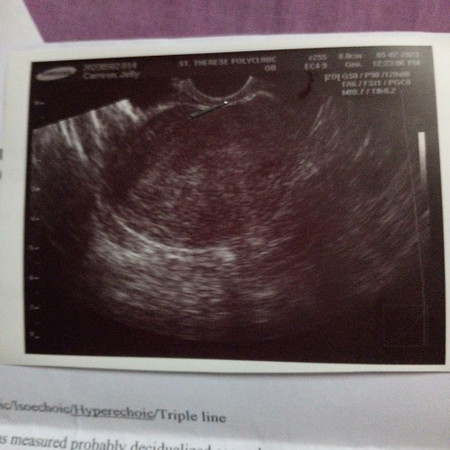

Ano nakalagay sa impression mo? Iba2 po kasi ang development yung iba early yung iba late, wag mgcompare dipendi yan kelan na fertilized